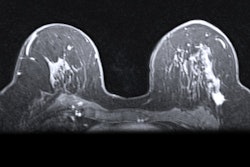

Ductal carcinoma in situ (DCIS) diagnosed with conventional breast imaging usually showed nonmass enhancement on breast MRI scans, with a larger median span for lesions than mammography and an increased cancer detection rate of 6.2%, in a study published August 3 in Radiology.

The group found that the median preoperative span was larger on breast MRI compared with mammography, at 19 mm versus 12 mm (p < 0.001). MRI also led to additional biopsies in 19.5% of cases, generating a 32% positive predictive value, a 6.2% additional cancer detection rate, and a 14.2% false-positive rate.

The investigators also found that smaller MRI span and focal nonmass enhancement were linked to success of a single wide-local excision (p < 0.001).